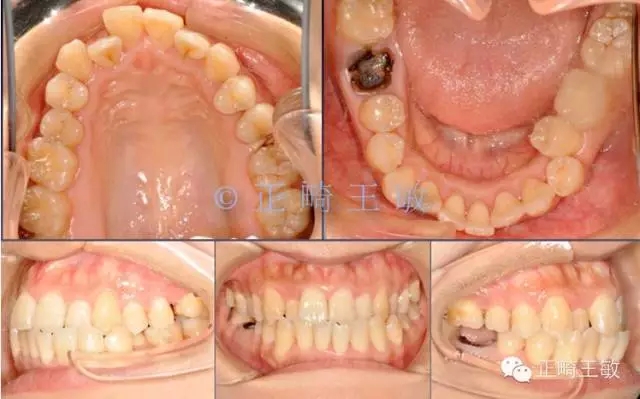

首先來看這樣一個病例:

30.webp.jpg

這樣的情況看起來很復雜,缺2個牙,三類關系,擁擠,又偏又反。如何處理?